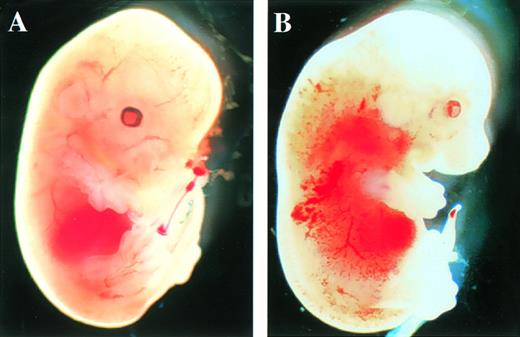

After the intercrossing of heterozygous mice, the genotypes of their litters were examined at 4 weeks of age by Southern blot analysis (Fig1B), and no homozygous mice were found. Because we did not observe the death of mice until 4 weeks of age, homozygous mice seemed to be lethal during gestation. To determine when embryonic lethality occurred, we analyzed embryos at various stages of gestation (Table 1). At E14.5, we observed no live homozygous embryos. At E12.5, some of the homozygous embryos were dead, as ascertained by the absence of heartbeat at the time of dissection. Therefore, we concluded that homozygous embryos died at E11.5-14.5. The appearance of homozygous embryos at E12.5-13.5 was edematous, with bleeding apparent under the skin (Fig 2).

Appearance of embryos at E13.5. (A) Wild-type littermate. (B) Appearance of the homozygous Mll embryo. Subcutaneous edema and hemorrhage are seen.

Fetal livers from Mll+/+, Mll+/mu, and Mllmu/mu littermates at E11.5 and E12.5 were examined histologically. Fetal liver cells, particularly hematopoietic cells, were slightly reduced in Mllmu/mu embryos compared with those in Mll+/+ and Mll+/mu littermates at E11.5 (Fig 3A and B). The decrease in hematopoietic cells was prominent in the livers of Mllmu/muembryos compared with those of Mll+/+ and Mll+/mu littermates at E12.5 (Fig 3C through F). In addition, the total number of cells in Mllmu/mu fetal livers was decreased at E12.5 in comparison with those of Mll+/+ and Mll+/mu littermates (Table 3). However, the appearance of fetal liver cells was similar among Mll+/+, Mll+/mu, and Mllmu/mu littermates in the liver stamp specimens stained with May-Grünwald/Giemsa. Erythroid, myeloid, and monocytic cells were present at various stages of differentiation in Mll+/+, Mll+/mu, and Mllmu/mu fetal livers (Fig 4A through D, Table 4). Megakaryocytes were also present in Mllmu/mu fetal livers (Fig 4E and F, Table 4). The presence of granulocytes and monocytes in Mllmu/mu fetal livers was also confirmed by fluorescence-activated cell sorter (FACS) analysis using anti-Mac1 and anti-Gr1 antibodies (Fig 5). We also confirmed the presence of macrophages in tissues of Mllmu/mu embryos by immunohistochemistry using the antimacrophage antibody F4/80 (Fig 6, see page 110). Further, we analyzed the components of peripheral blood at E12.5 and found mostly nucleated red blood cells, with few leukocytes and a few anucleated red blood cells derived from definitive erythropoiesis in fetal liver. These findings were similar among Mll+/+, Mll+/mu, and Mllmu/mu embryos (Fig 7, see page 115).